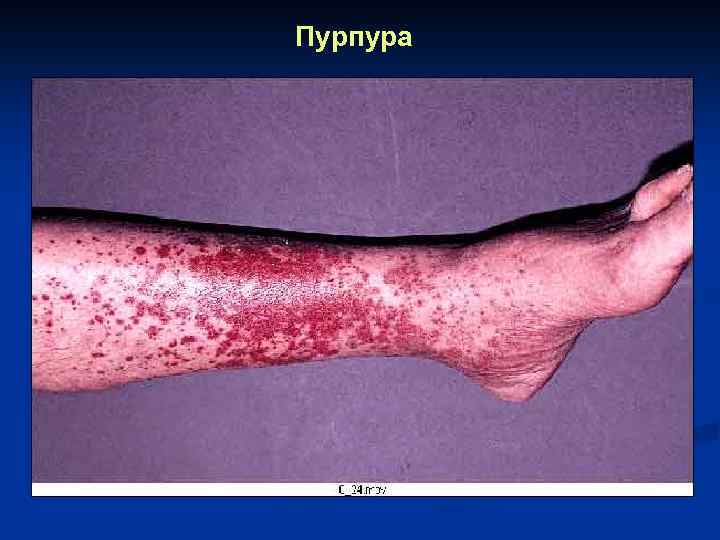

Пурпура